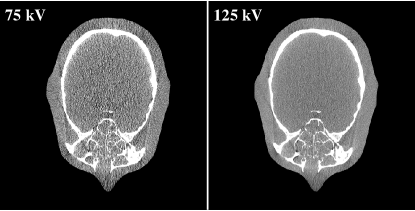

The algorithm was also evaluated using experimental data from an anthrophomorphic head phantom scanned on a cone-beam CT (CBCT) benchtop system. The distance of source to isocenter and source to detector are 1000 mm and 1500 mm, respectively. A total of 655 projections were evenly acquired in 360 degree rotation with 2×2222\times 2 rebinning mode and narrow collimation to avoid scatter radiation. Tube potentials of high and low-energy spectra were 125 kVp and 75 kVp, respectively. Both of the spectra were filtered with a 6 mm aluminium filter.

Fig. 4 shows low- and high-energy CT images of the head phantom. For the experimental evaluation, the benchtop CBCT system has used a flat detector with 0.6 mm thickness of CsI. To better estimate the spectrum, energy dependent efficiency has been taken into account. Fig. 5 depicts spectrum estimated with the anthrophomorphic head phantom with detector efficiency incorporation. The initial spectrum is the hardest spectrum of the model spectra. As can be seen, the estimated spectrum matches the raw spectrum well. The mean energy difference and NRMSE are 0.71 keV and 7.5%percent7.57.5\%, respectively. Note that we do not directly measure the raw spectrum in this case, instead, the well-validated spectrum generator SpekCalc is used to generate the raw spectrum with matched x-ray tube specifications.

Figure 4: Low- and high-energy CT images of the experimental head phantom. Display window: [-300HU, 300HU].